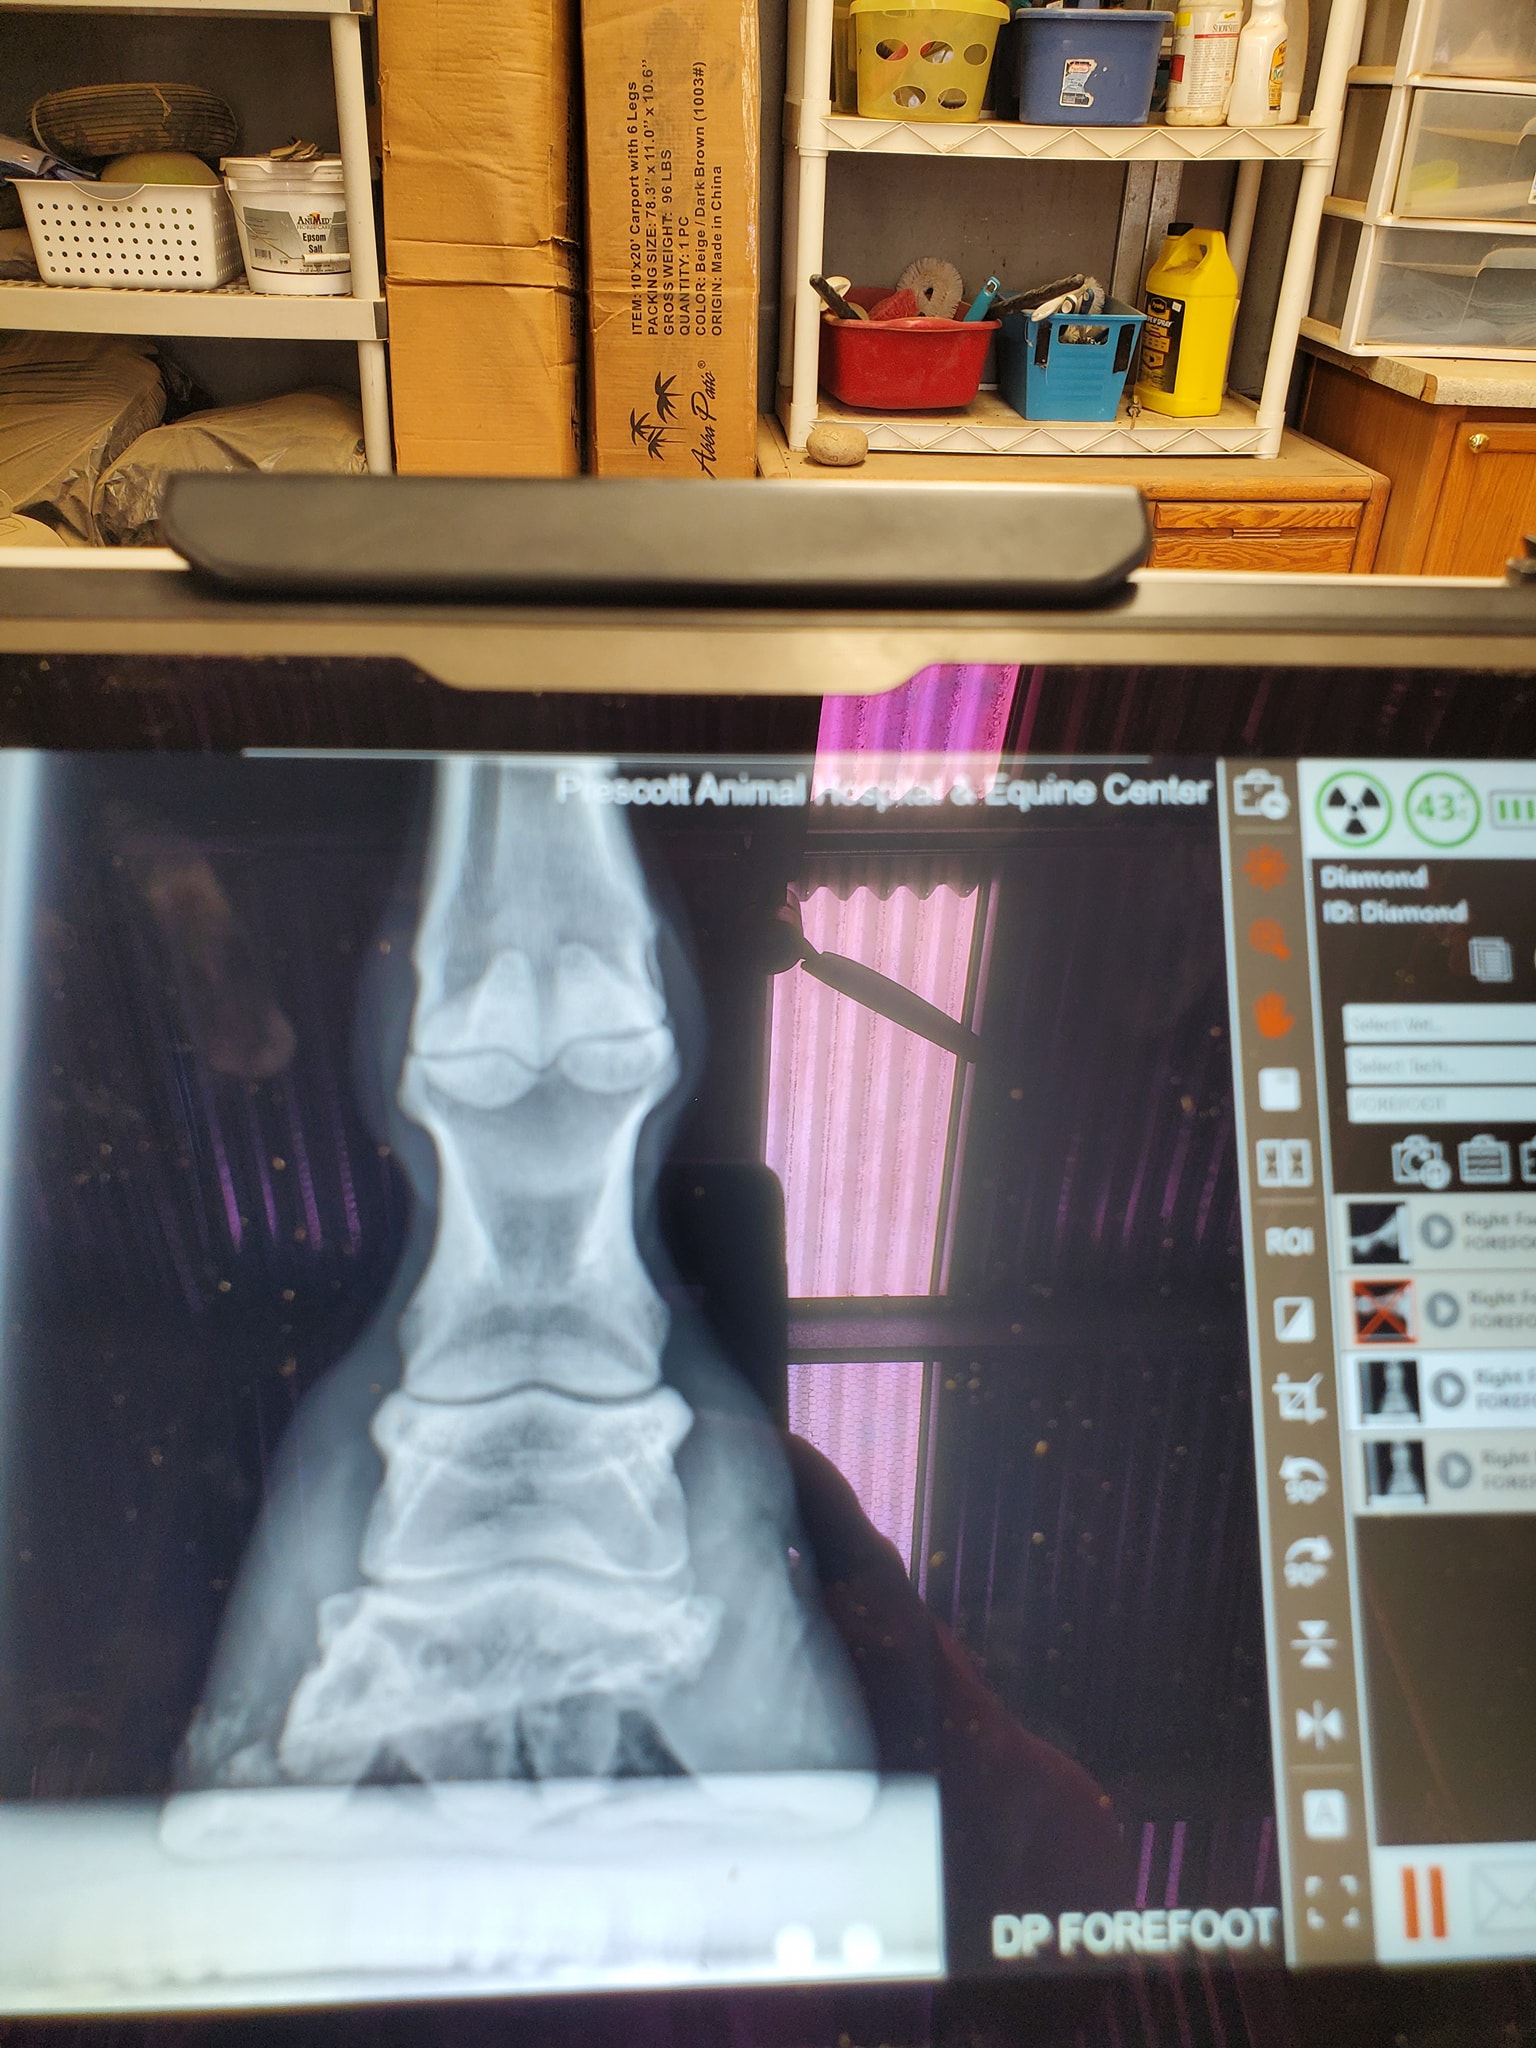

However, the coffin bone is still only half a coffin bone and it is pointed down and sideways (see his most recent x rays). Because he does get uncomfortable sometimes, we give him the very best of hoofcare and very special aluminum shoes.